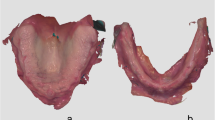

A virtual central incisor was generated from the contralateral central incisor (21) by using the mirror tool (Fig. 2e) and saved in an independent file. The latter was then imported into a second CAD software (Freeform, 3D Systems, US) and two small cylindrical volumes were created into the palatal side of the virtual incisor to create a retention area (Fig. 3a and b). In the same software, limits of the denture base were virtually designed by using the point and click tool. The denture was generated with a volume (average thickness of 2.5 mm) corresponding to a replica of the patient palatal surface (Fig. 3c and d). Data generated were then exported to a 5-axis milling machine (DWX 52 DC, Roland, Japan) and the resin artificial incisor was made by milling a stratified ivory disk of PolyMethylMethAcrylate (PMMA) (Trilux, Vipi, Italy). The denture base was produced from a disk of pink PMMA (Ivobase CAD, Ivoclar, France). The incisor was bonded onto the denture base using an adhesive agent (Probase, Ivoclar, France). Two metal clasps were manually designed and manufactured on a model printed in parallel (ProJet 3500 HD, 3D Systems, US) by using clap wires (Wironit, Bego, France). Clasps were integrated into the denture base with autopolymerisable resin (Probase, Ivoclar, France) (Fig. 3e). Upon reception to the clinics (three weeks after digital impressions), the removable denture was cleaned, and finishing and polishing were checked.

Conception and manufacturing of the immediate removable partial denture. Both files were imported into a second CAD software and two cylindrical shapes were then subtracted from the palatal side of the artificial incisor to create a retention zone (a and b). The volume corresponding to the denture base was generated as a replica of the patient palatal surfaces (c and d). The incisor and the denture base were independently milled, and then were bonded together. Two metal clasps were manually integrated in the denture base with autopolymerisable resin (e)